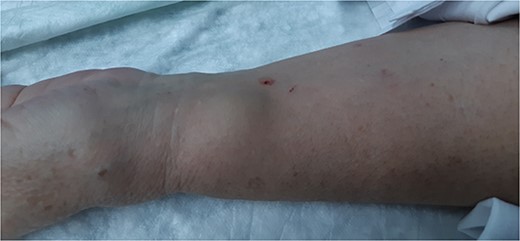

A 62-year-old female with a personal history of atrial fibrillation, hypertrophic cardiomyopathy, heart failure (Classes I–II/IV—New York Heart Association), arterial hypertension, dyslipidemia, Type II diabetes mellitus and smoking underwent two coronary angiography 6 months apart, both through left radial access with a 6Fr sheath and mechanical compression with PreludeSync. Punctures were performed by the Cardiology Department without an ultrasound and without any signs of difficulties in hemostasis. In the last procedure, the patient underwent coronary revascularization with stents and was medicated with dual antiplatelet therapy. The patient developed a pulsatile and expandable mass in the left wrist, 3 weeks after the last coronary angiography (Fig. 1). On physical examination, a painful, expandable and pulsatile mass with a murmur was identified. Complaints of paresthesia or signs of hand ischemia were not present. On duplex ultrasound, the mass had a longitudinal diameter of 2.2 cm, with a narrow neck and turbulent ‘yin-yang’ flow, compatible with a PA of the left radial artery. The patient underwent PA resection with arteriorrhaphy (longitudinal stitches), without any complications, and was discharged 24 h postoperatively (Figs 2 and 3). At 1-month follow-up, the patient was asymptomatic, presenting a palpable radial pulse and did not report any sensory deficits.

In the case described, the resection and primary repair of the radial artery defect was chosen taking into account the size of the PA and the mass effect produced along with the relatively restricted arterial wall lesion.